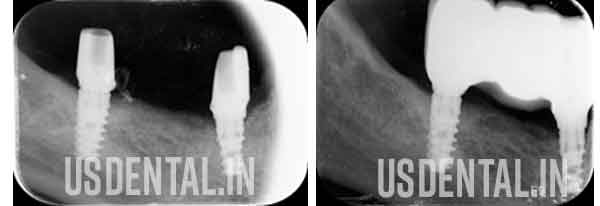

Dental Implants for Lower Right Teeth Replacement and Healing Process

Two dental implants placed at lower right side for teeth replacement. Followed by implant surgery, the patient has advice to wait for 3 months so the implant gets stronger.

After completion of healing measurement taken and sent to the lab for fabrication of implant supported bridge.

After an impression and required trial, the implant supported bridge was fixed on the dental implant. Upper old bridge also changed along with the lower implant procedure.